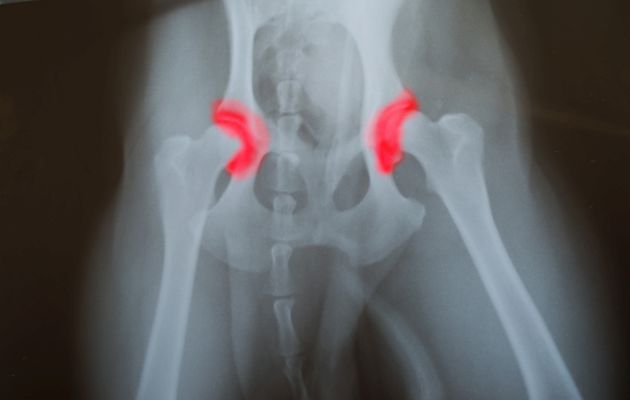

În plus, în unele cazuri există și displazia de dezvoltare a șoldului. Asta înseamnă că șoldul nu este stabil, din cauza faptului că elementele acestei articulații s-au dezvoltat anormal. Cavitatea este aproape plată, iar capul femurului a alunecat total sau parțial în afara ei, potrivit medicilor.

Tal valg poze

Iată poze care ilustrează această afecțiune, ca să îți fie mai ușor să o recunoști: